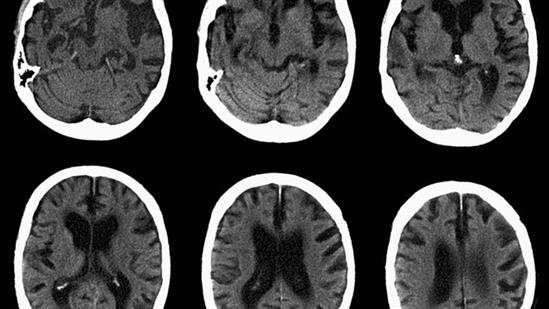

Ý nghĩa thứ 2, và cũng là ý nghĩa chính của các nhà khoa học khi nghiên cứu công nghệ mới này chính là phục vụ cho sức khỏe của con người. Não bộ là phần quan trọng nhất của cơ thể con người, và do đó mọi bước tiến trong nghiên cứu não bộ đều ảnh hưởng không nhỏ tới sự sống của rất nhiều bệnh nhân trên toàn cầu. Nhưng vì lí do đạo đức, việc nghiên cứu trên não bộ luôn gặp những khó khăn và rào cản xã hội (hãy thầm cảm ơn các nhà khoa học vì họ đã vượt qua rất nhiều điều để đem lại cho chúng ta những kiến thức như ngày nay). Vậy nên nếu bạn có một bộ não nhân tạo mô phỏng y hệt một bộ não người, đó sẽ là công cụ tuyệt vời để nghiên cứu trị các căn bệnh như Alzheimer và Parkinson.

Đấy là về phương diện nghiên cứu, còn về phương diện chữa bệnh, việc tái tạo não nhân tạo cũng có tầm ảnh hưởng tương tự như các tái tạo các bộ phận khác trên cơ thể (tất nhiên là ở độ khó cao hơn nhiều). Không phải ai sinh ra cũng có một não bộ hoàn chỉnh như bao người khác. Những trường hợp bị các căn bệnh như động kinh hay suy giảm chức năng của cơ thể do khiếm quyết não là không hề thiếu, và trong phần lớn trường hợp, sự tương tác của con người để giải quyết căn bệnh là rất khó khăn. Nhưng nếu chúng ta có thể tạo ra các mô não nhân tạo để tu bổ những khiếm quyết đó, đấy sẽ là cơ hội để những người bệnh có thể có một cuộc sống bình thường mà họ mong muốn.